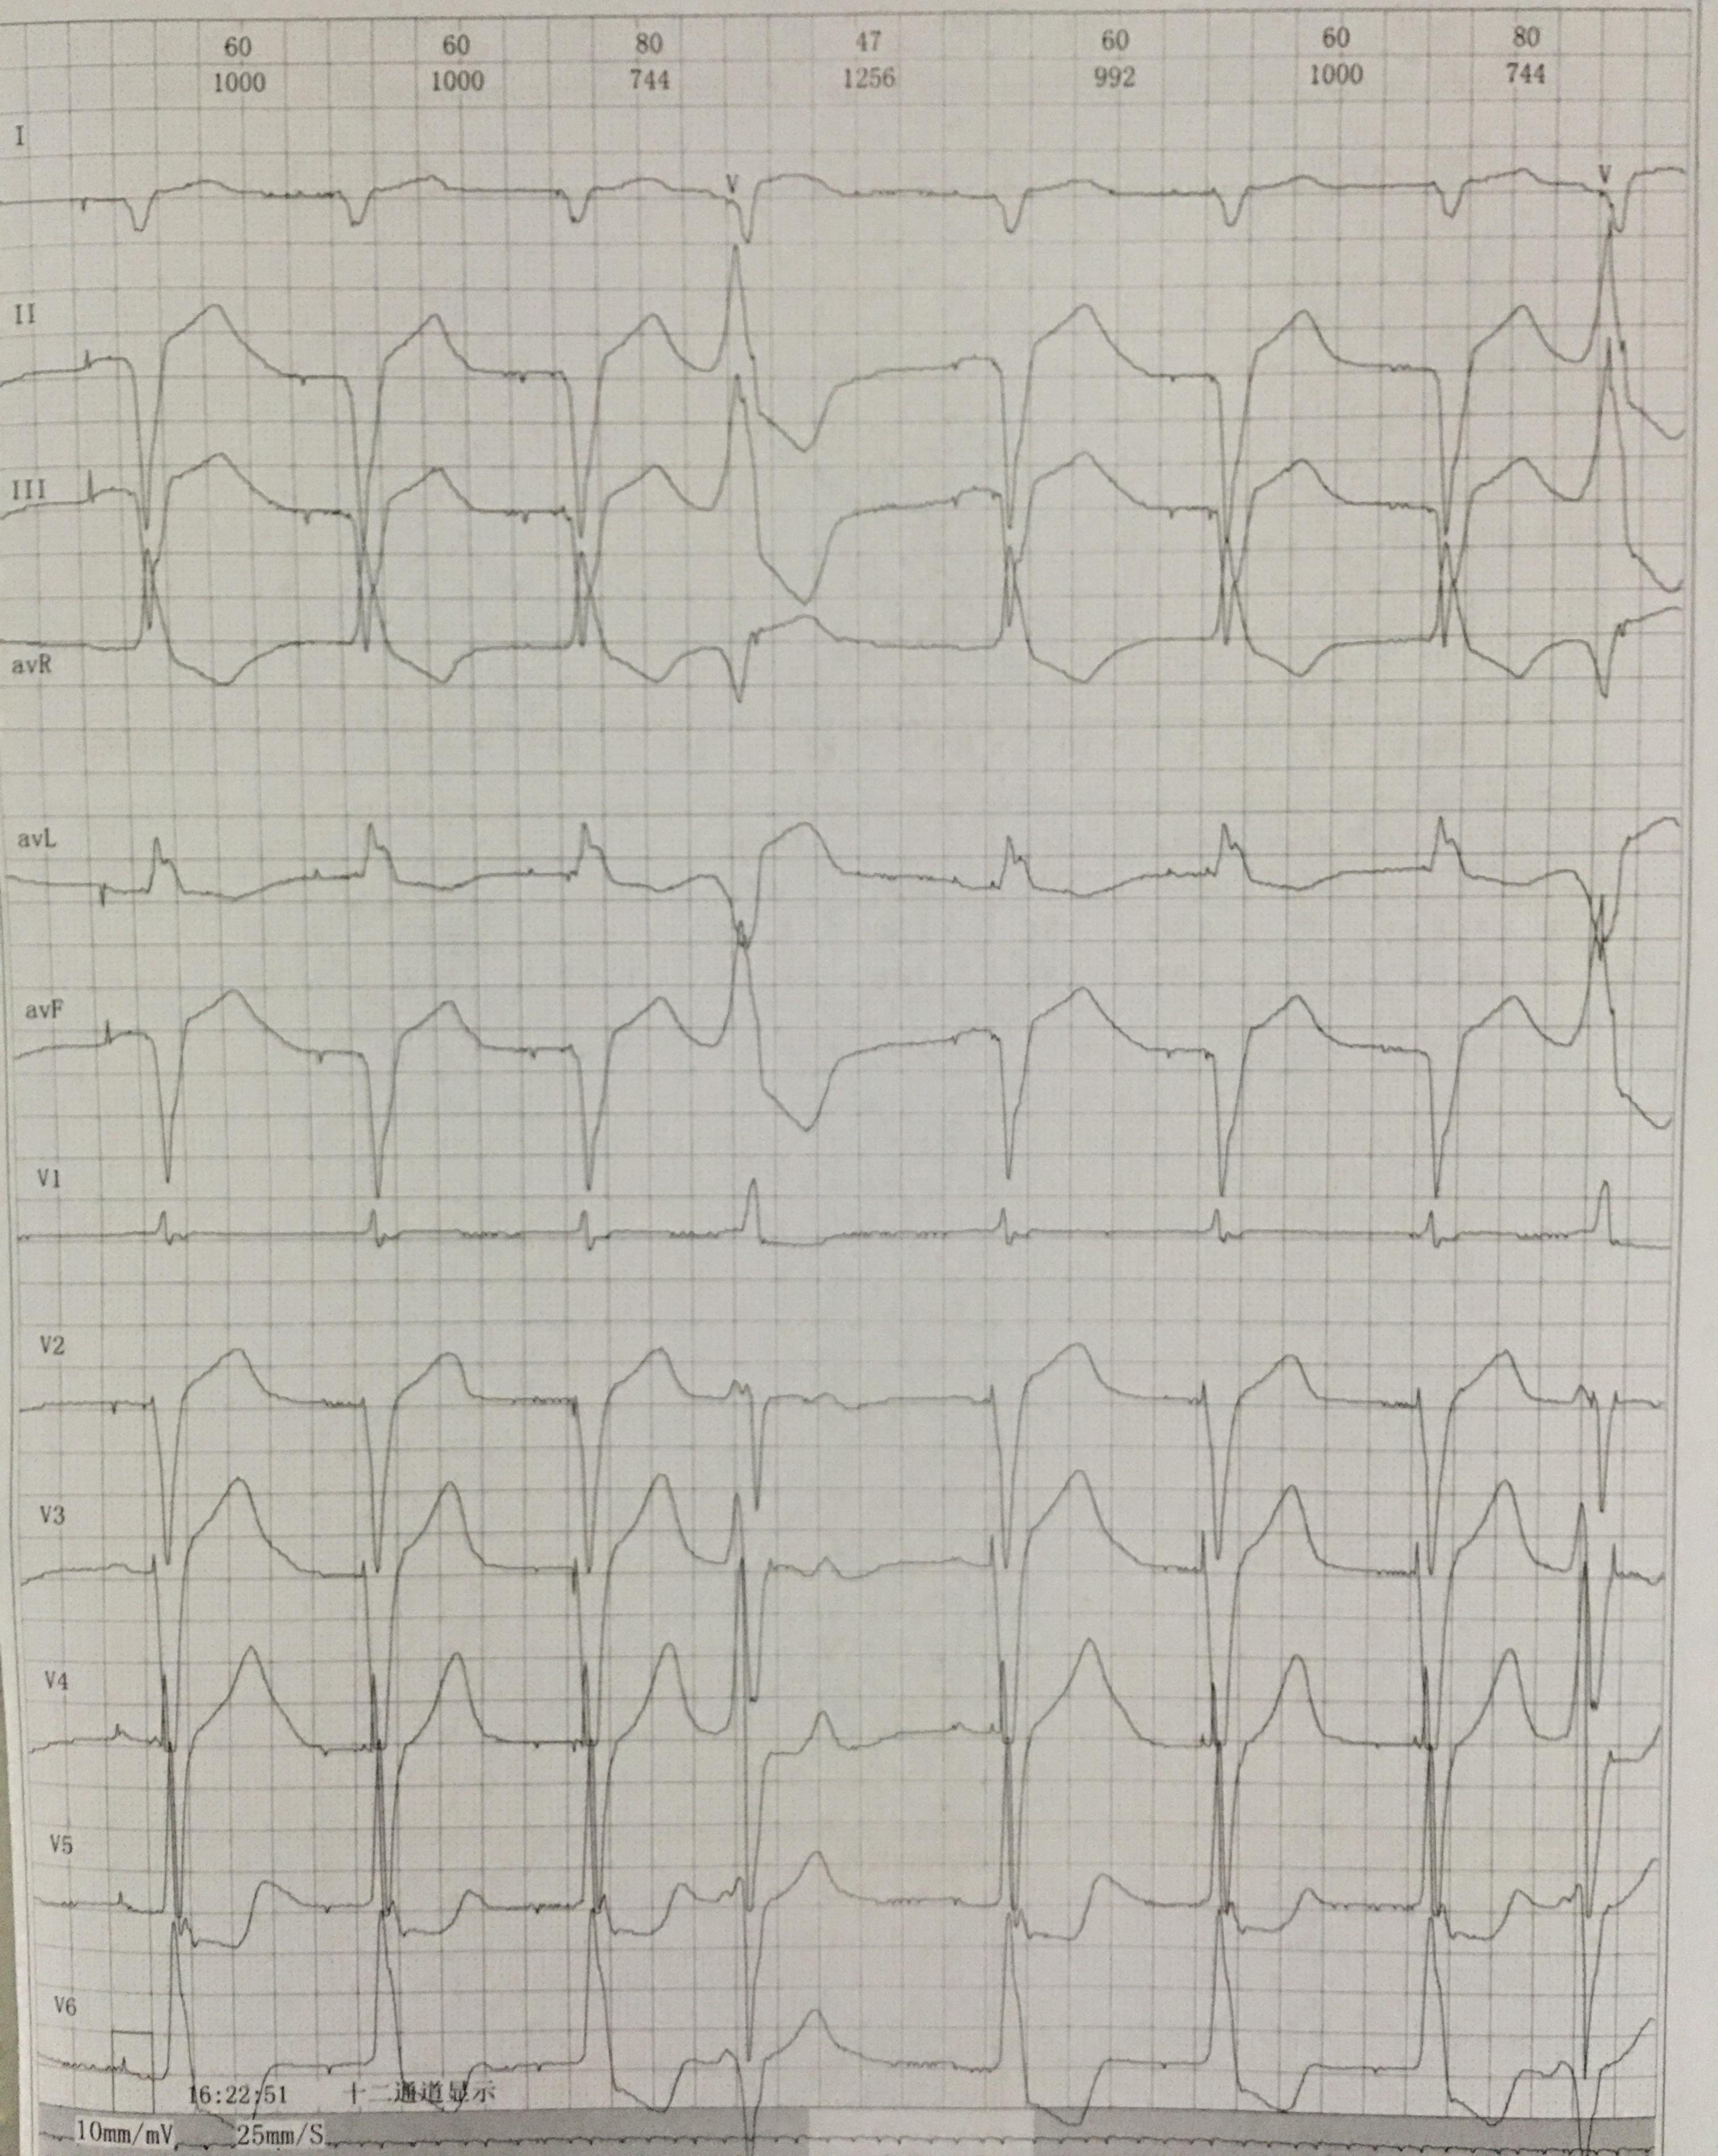

Ⅲ°房室传导阻滞

三度房室传导阻滞

[心电图分析] 三度房室阻滞